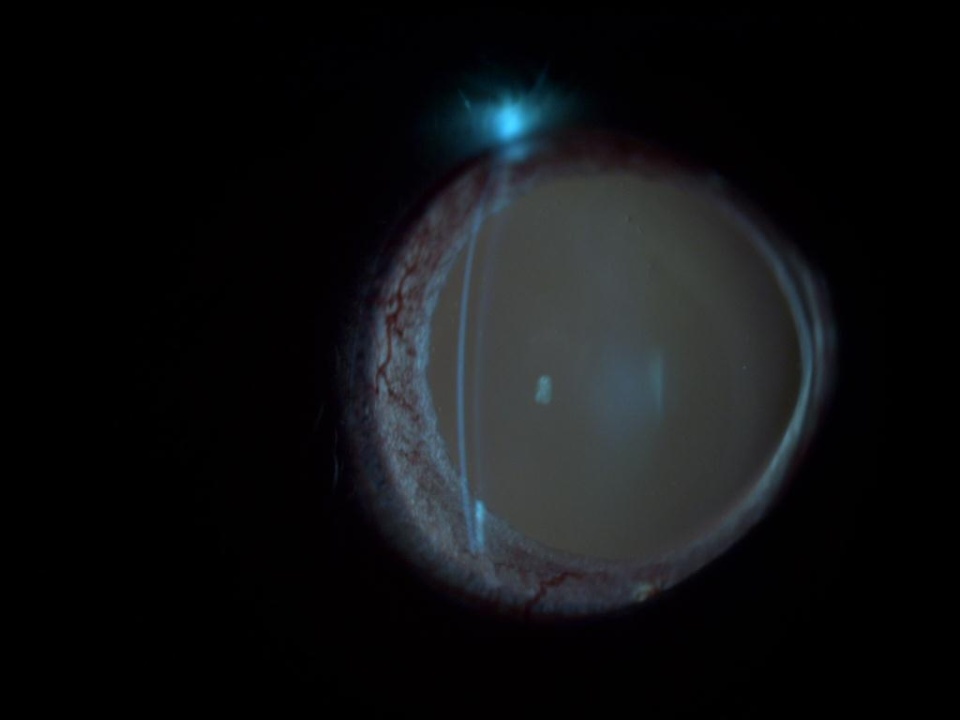

1103_92.jpg